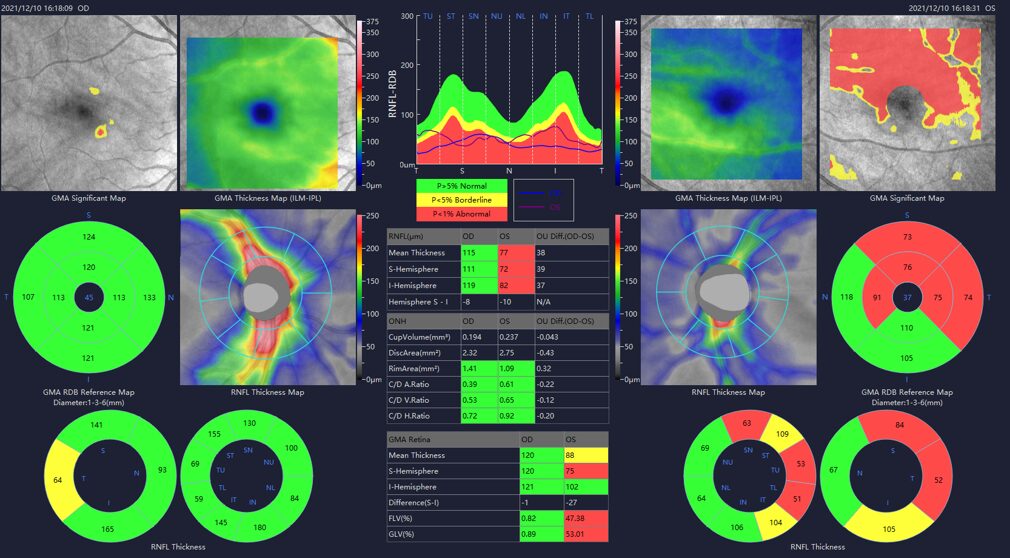

Geavanceerde glaucoomanalyse met gedetailleerd iHealth-rapport

- 6×6 mm papil- en retinale zenuwvezellaag analyse met meting van cupgebied, randgebied en cup/disc-verhouding

- 7×7 mm ganglion-macula-analyse meet de afstand van de interne begrenzingsmembraan (ILM) tot de buitenzijde van de binnenste plexiforme laag (IPL), die de binnenste 3 lagen van het netvlies vormt (NFL, ganglioncellagen, IPL), inclusief significantiemap (GMA-dikte vs. normatieve database)

- 15×9 mm 3D-scan voor iHealth-rapport met uitgebreide analyse van papil en macula

ONH en RNFL analyse

- 3D Disc scan uit 512 horizonatle lijne in een 6 mm square area

- Bilateral 3D disc reporst

Ganglion Cell Complex analyse

- Ideale predictor om vroegtijdig glaucoom op te sporen en op te volgen

- De GMA diktekaart wordt vergeleken met de normatieve database om snel via kleurcodes een evaluatie te kunnen maken

- De PSD en de MD zijn bijkomende factoren die de graag van vroegtijdig verlies en de uitgebreidheid evalueren.